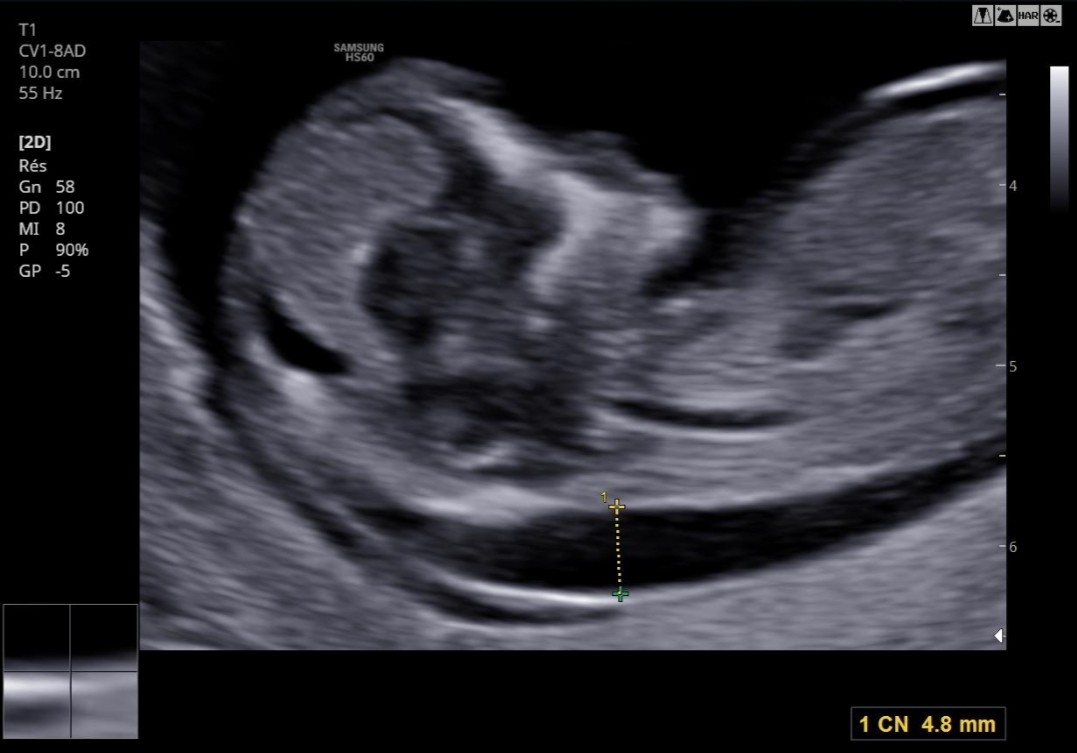

Ces Petits Millimetres Cn 4 8 Mm Lettre A Mon Bebe Tetu Amniocentese Forum Grossesse Amp Bebe Doctissimo